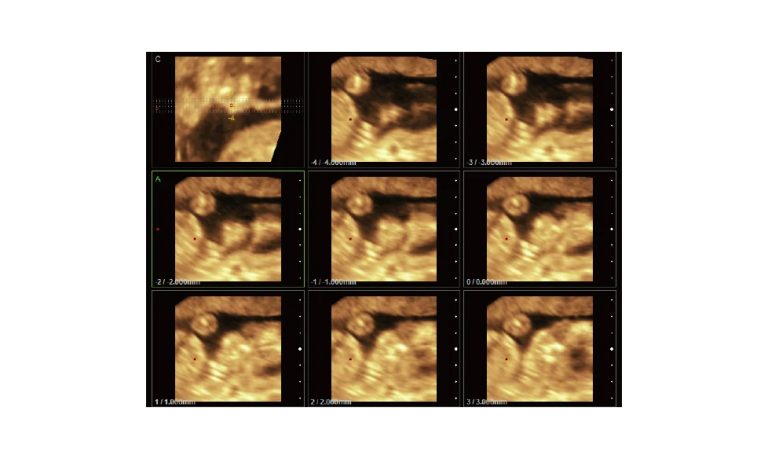

SonoScape Pro Pet E11

Smart Imaging

Introducing the first portable ultrasound with the C-Field+TM platform, redefining diagnostic imaging. Designed for veterinarians, it delivers unmatched clarity, ultra-fast processing, and seamless adaptability for all species. Experience Smart Imaging, Heartfelt Care—anywhere.

Equipped with cutting-edge veterinary software and optimized workflows, it embodies our commitment to Smart Imaging, Heartfelt Care – Wherever Their Journey Leads, with unparalleled performance and adaptability, this innovative system empowers veterinarians to provide exceptional care across all diagnostic applications,